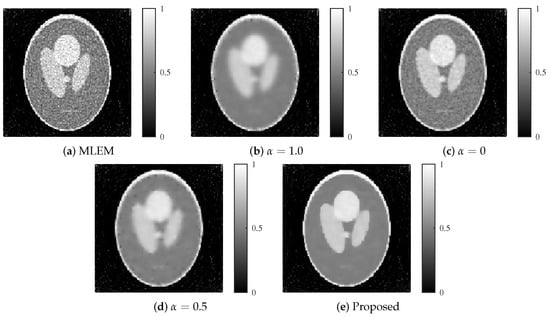

Figure 6.

Reconstructed images for each method with an SNR of 30 dB. (a) MLEM, (b) MLEM with L1 regularization (), (c) MLEM with L2 regularization (), (d) MLEM with ElasticNet regularization ( fixed), and (e) proposed dynamic ElasticNet regularization. The proposed method exceled in both noise reduction and image detail preservation.

The images reconstructed by each method are presented in Figure 6 and Figure 7. At an SNR of 30 dB, the method with a fixed (L1 regularization) achieved strong noise suppression; however, it also resulted in excessive smoothing, particularly at the edges. In contrast, the method with (L2 regularization) showed slight noise at 30 dB but exhibited substantial noise artifacts under the more challenging 25 dB condition. The fixed ElasticNet method with provided a balance between noise suppression and edge preservation, yielding intermediate image quality between the and cases. However, it failed to remove noise sufficiently at 25 dB. In comparison, the proposed method successfully achieved both high-level noise suppression and edge preservation for both noise levels.

First, we present the results of the modified Shepp–Logan phantom with noise levels of 30 and 25 dB. The graphs of the evaluation function and the number of iterations k are shown in Figure 5a,b. The parameters utilized in Equations (9) and (11) were , and , for 30 and 25 dB, respectively. The value of was 0.06 for both noise levels, which was determined as the optimal value from the experimental results. The value was set to 0.01 for all regularization methods.